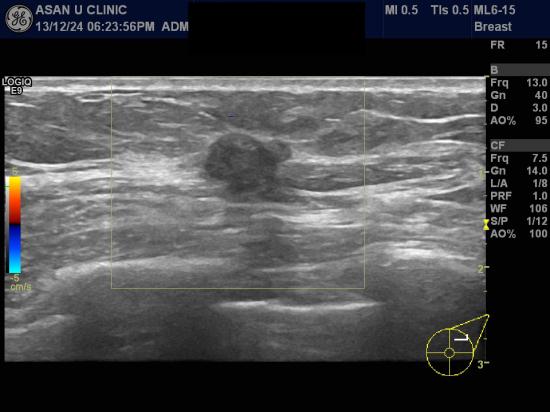

건강검진상 이상소견있어 내원한 51세 여성분입니다.

본원에서 실시한 유방초음파상 1.08 cm의 혹이 좌측유방에 있었고

조직검사를 실시하여 침윤성 유방암으로 진단되셨습니다.